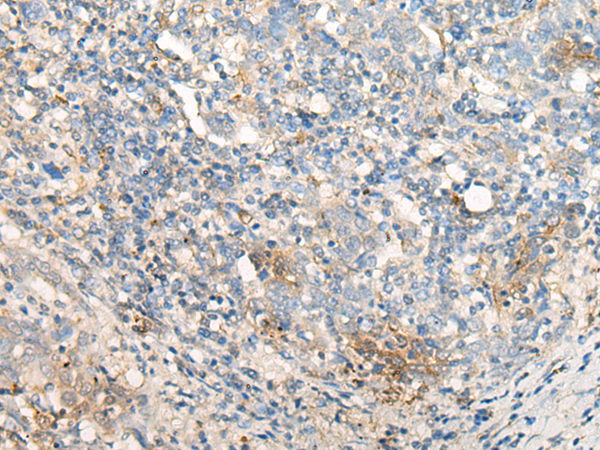

分类: 科研抗体货号: P09630别名: TSK3; SPOGA3; STK22C; STK22D应用: IHC反应种属: Human, Mouse